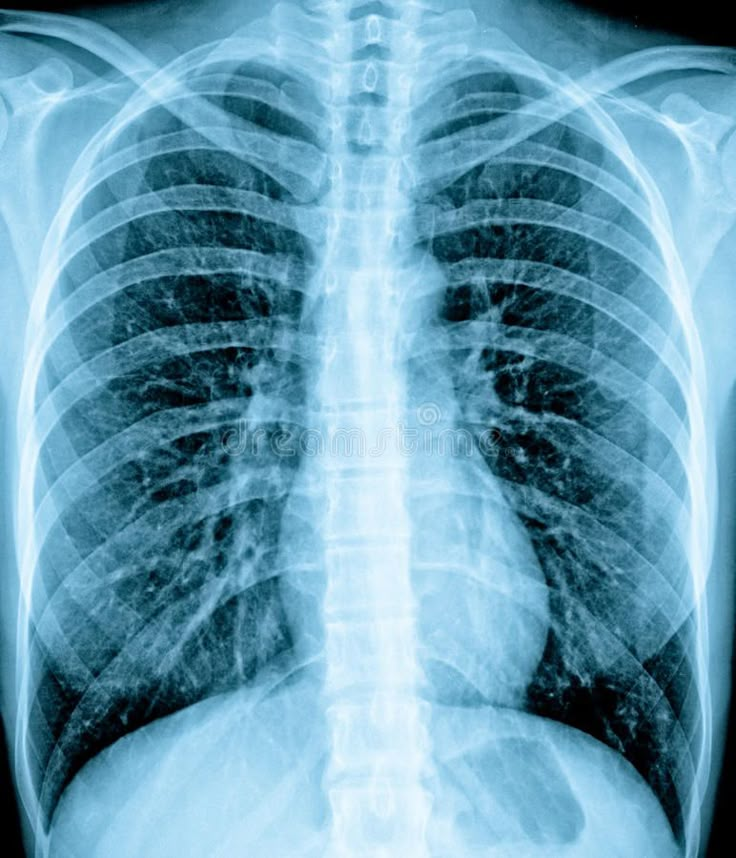

Radiography trains professionals in medical imaging techniques, radiation safety, and diagnostic procedures essential for modern healthcare.

- Perform diagnostic imaging procedures accurately and safely

- Interpret images for preliminary findings